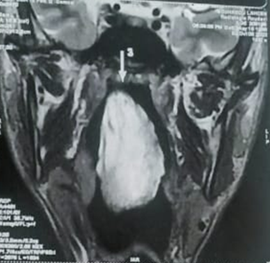

were clear (Figure 2). MRI of the

face revealed an oblong mass filling the lumen of the cavum originating in the

right nasal cavity opposite the middle meat and extending into the oropharynx (Figure 3). At surgery, the

Figure 3. Coronal and

sagittal sections of a facial MRI: Insertion site of the mass in the middle

turbinate and extension into the nasopharynx (a) and oropharynx (b).